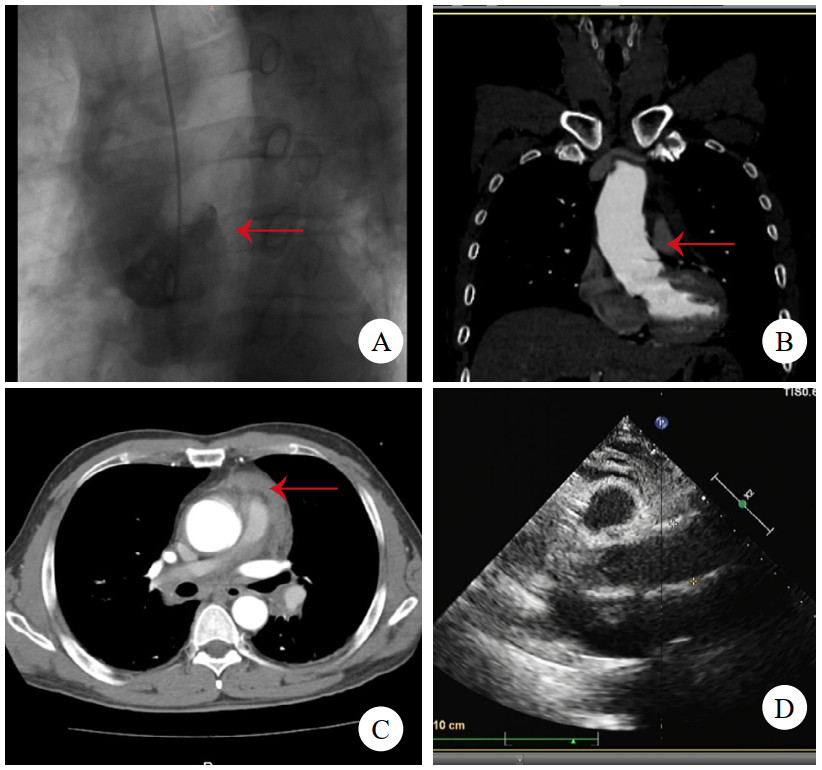

病例2,男,47岁,因“突发背痛伴胸闷1 h”入院。查心电图提示下壁导联ST段抬高0.1 mv,TTE提示节段性室壁运动异常,升主动脉及窦内径增宽,肌钙蛋白阴性,考虑“急性心肌梗死”。行急诊冠脉造影术,见冠状动脉通畅,加行主动脉造影见根部后壁斜行龛影(图 2A)。予查主动脉CTA,见主动脉根部左冠状动脉开口上方条状影(图 2B),该处主动脉直径为44 mm,升主动脉周围少量心包积血(图 2C),提示LIT。建议急诊开胸手术,患方自行至外院行升主动脉置换术,术中所见符合LIT,术后2个月至本院复查TTE,见升主动脉人工血管通畅(图 2D),无室壁运动异常。后门诊随访5年,情况平稳。

| 注:A为主动脉造影,箭头示根部后壁斜行龛影;B为主动脉CTA,箭头示左冠状动脉开口上方条状影;C为箭头示升主动脉周围少量心包积血;D为TTE见升主动脉人工血管通畅 图 2 例2患者主动脉根部造影、术前CT及术后TTE影像 |

病例3,男,60岁,因“半小时前晕厥1次”就诊。送入抢救室时见患者大汗淋漓,显著呼吸困难,查体:心率97次/min,血压76/52 mmHg(1 mmHg=0.133 kPa),精神极软,颈静脉怒张,心音低钝,未及心脏杂音。立即查床边TTE,见大量心包积液(图 3A)。符合心包填塞,予心包穿刺,见血性液体流出约100 mL后,患者胸闷缓解,心率下降,血压138/88 mmHg。查主动脉CTA,见升弓交界靠上腔静脉侧LIT(图 3B,C,D),该处主动脉直径为31 mm,局部外膜薄层血肿形成。建议手术,患方拒绝,在抢救室留置6 h后生命体征突然消失,后宣布临床死亡。

| 注:A为TTE,箭头示大量心包积液伴血块;B为CTA横断面,箭头示内膜片;C为CTA冠状面,箭头示内膜片;D为CTA多平面重建,箭头示内膜片 图 3 例3患者TTE及CT影像 |